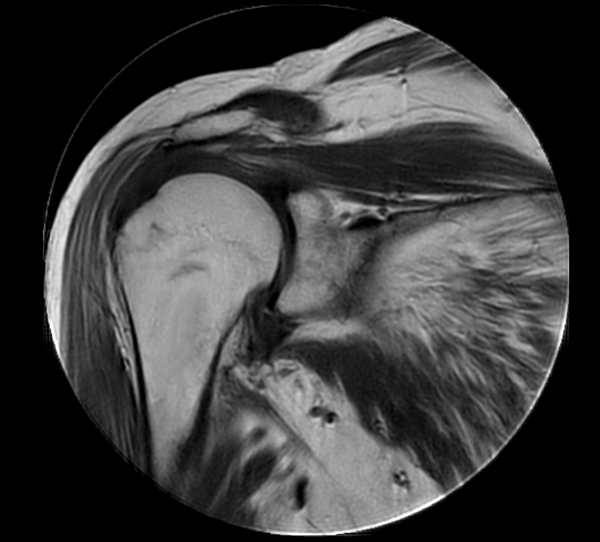

Coronal MultiVane XD - T1w TSE